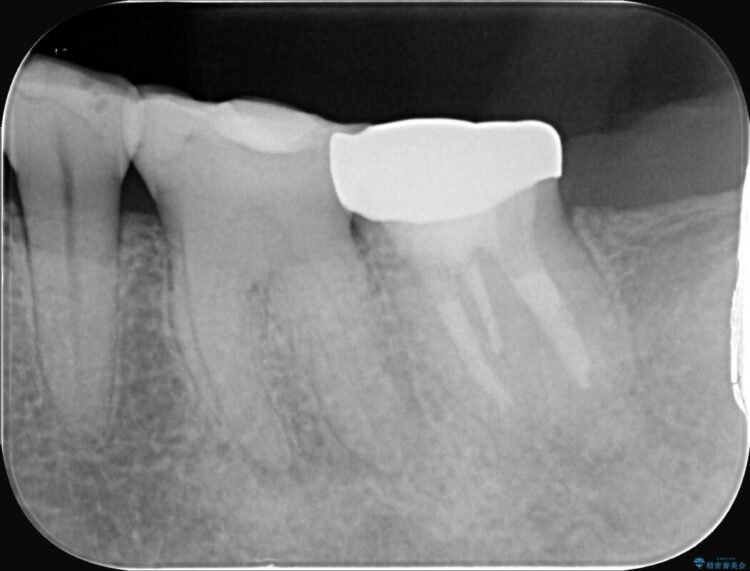

診察の結果、不可逆性歯髄炎(歯の神経の重度の炎症)と診断。

レントゲンを確認すると、歯髄腔が狭くなり根管が石灰化している難症例でした。